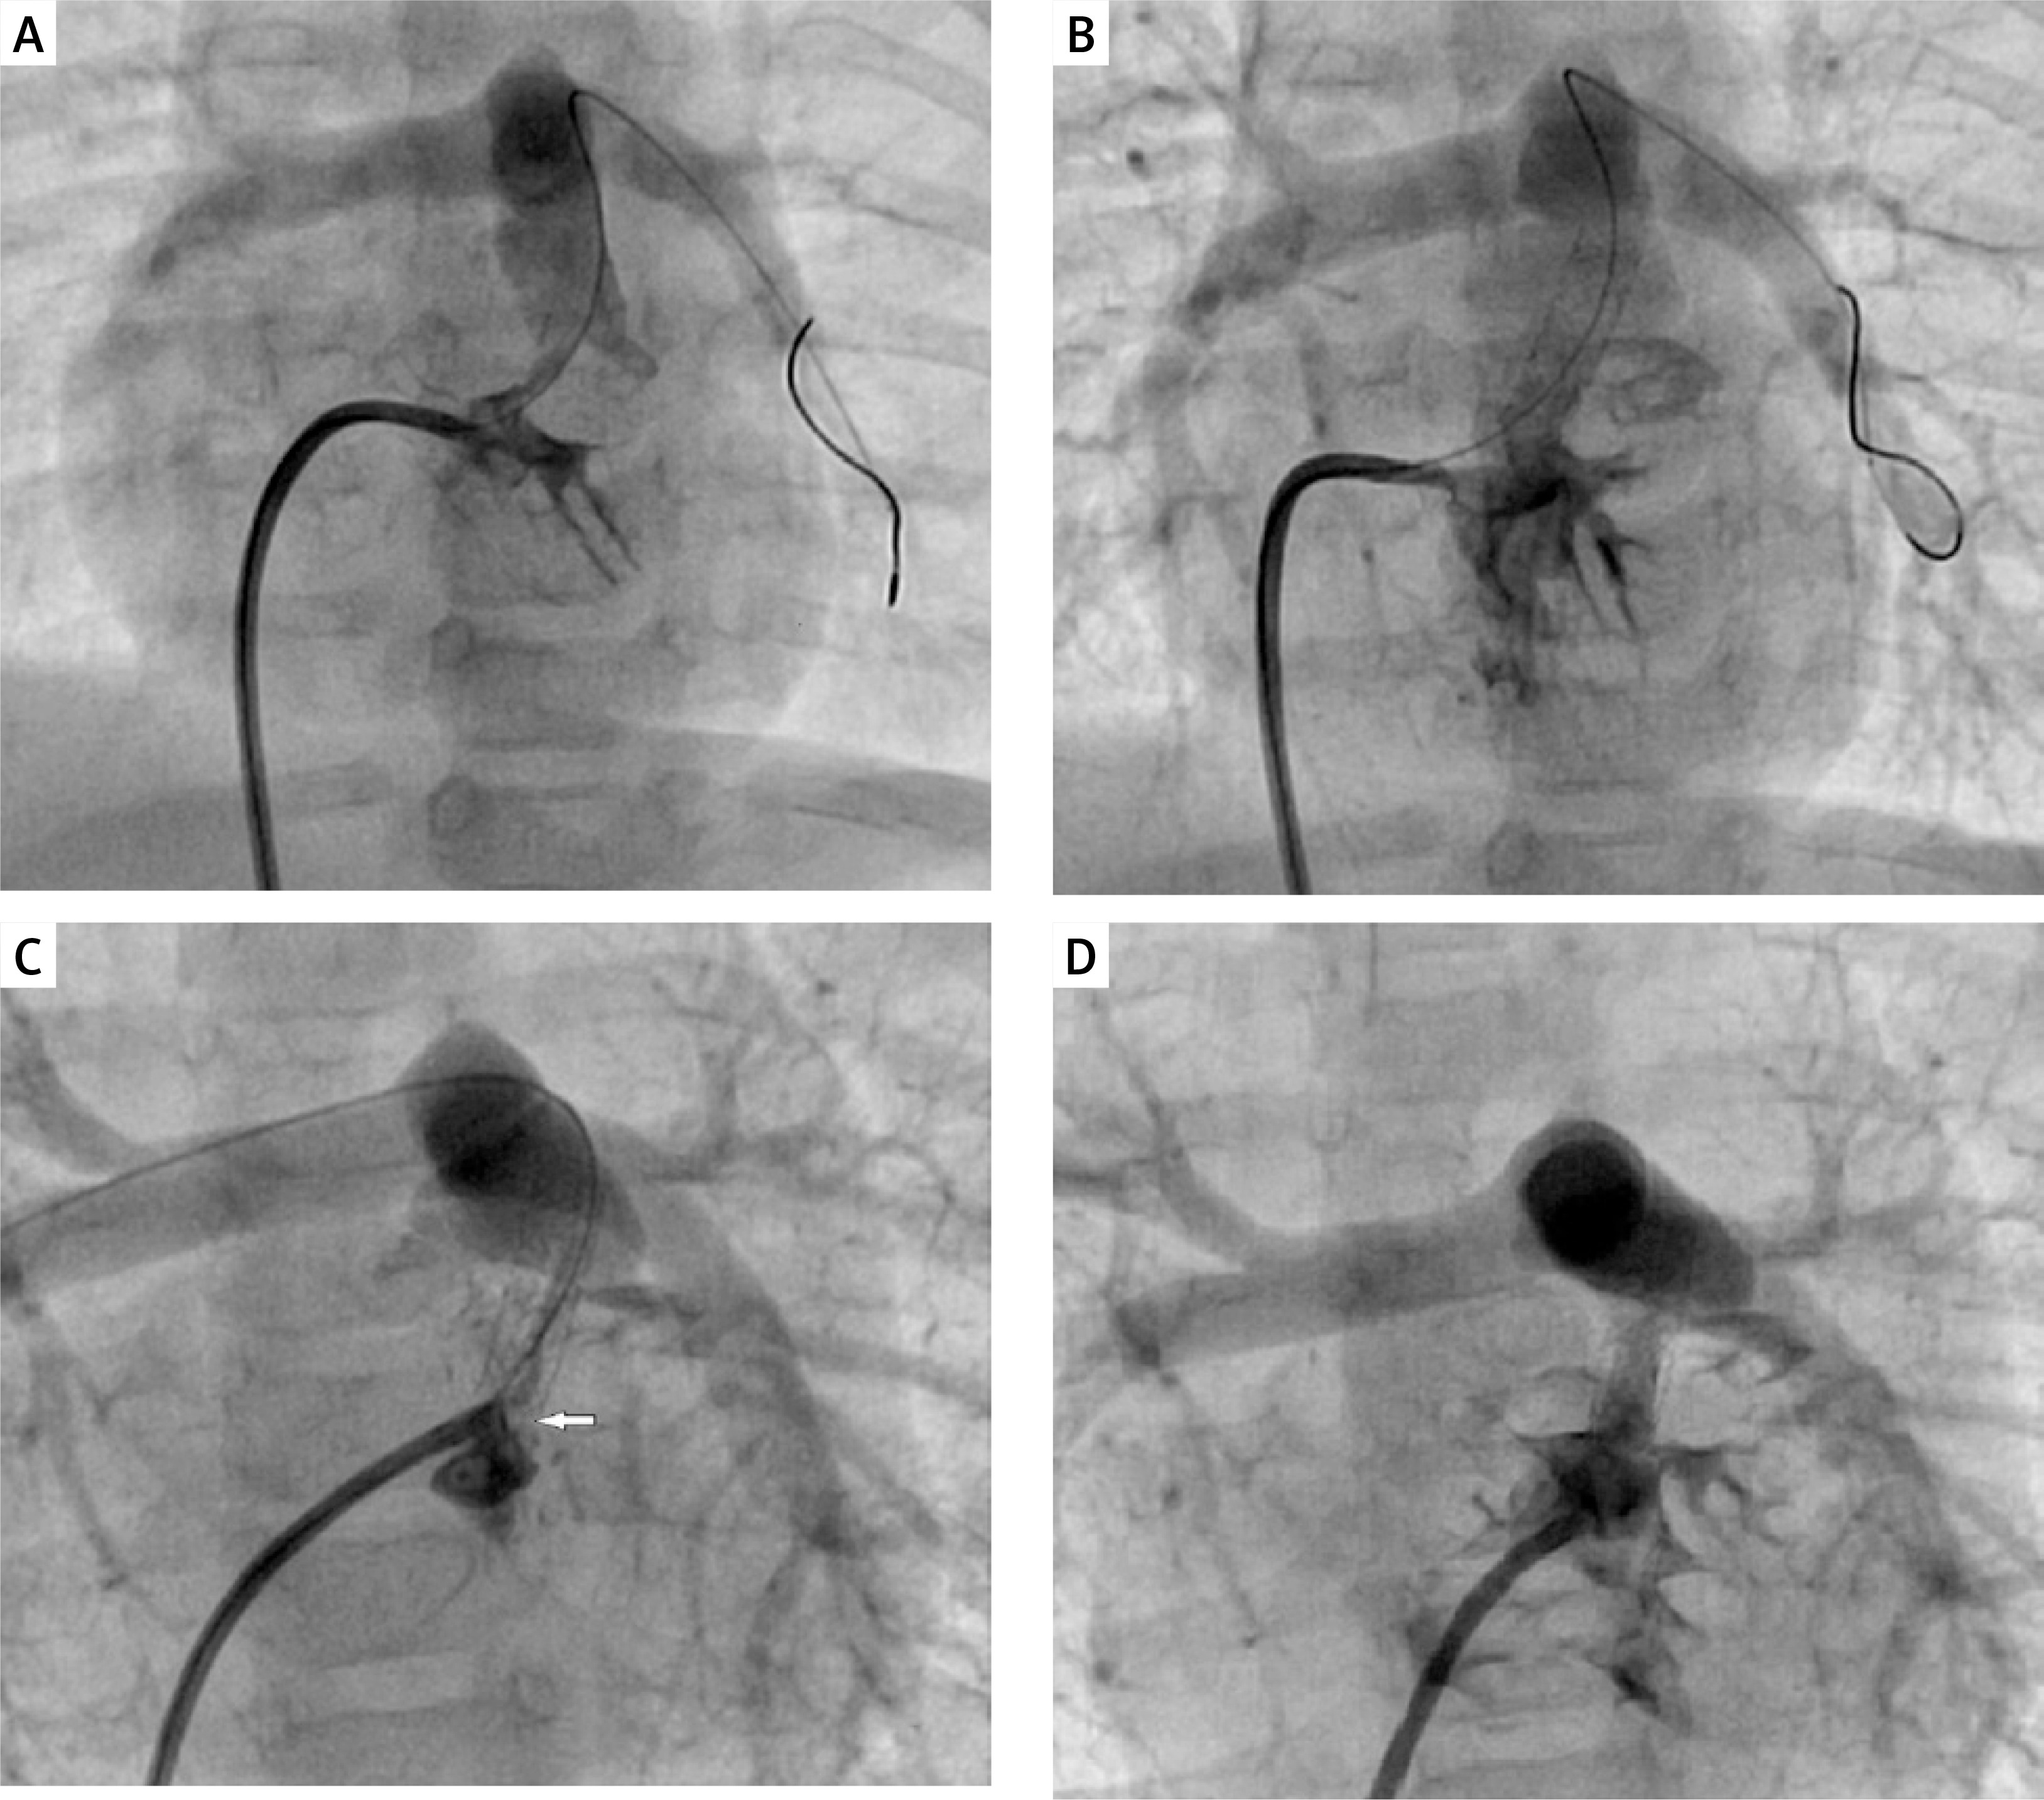

Figure 2

Right ventricular outflow tract (RVOT) stenting procedure in a 3.6 kg neonate with tetralogy of Fallot and recurrent stenosis occurred at the proximal stent end within 3 months of initial stenting. A – Initial right ventricular outflow tract angiogram in 30° right anterior oblique and cranial angulation. B – 4 mm 16 mm long coronary stent in position. Saturations improved from 72% to 89%. C – Progressive muscular narrowing below the stent (white arrow). D – The muscular stenosis was treated by restenting the outflow tract, with the 4.5 mm 12 mm stent covering the muscular band proximally and extending telescopically well into the prior stent. Saturations improved from 68% to 92%